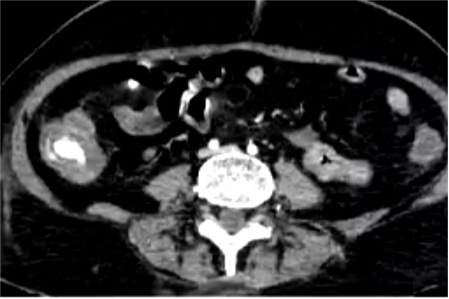

4. 技术要点急性消化道出血,生命体征稳定患者,CTA提示升结肠造影剂外溢

(1)操作流程·诊断性血管造影:用5F导管插管至肠系膜上/下动脉,寻找造影剂外溢(活动性出血)直接或间接征象 · · 超选择插管:通过同轴技术引入3F微导管,尽可能将导管送至直动脉(vasa recta) 或出血点最远端 · · 栓塞:首选微弹簧圈(2-3mm × 20-30mm),放置2-3个即可;也可用聚乙烯醇颗粒(>250μm);禁用液体栓塞剂(如酒精),因其肠坏死率高 · · 终点:造影证实外溢停止,同时保留近端和远端血流(不牺牲侧支循环) · (2)栓塞程度:多少算够?多少算多?理想情况:仅栓塞出血点所在的直动脉 若无法超选至直动脉,可栓塞边缘动脉(marginal artery),但必须确保: